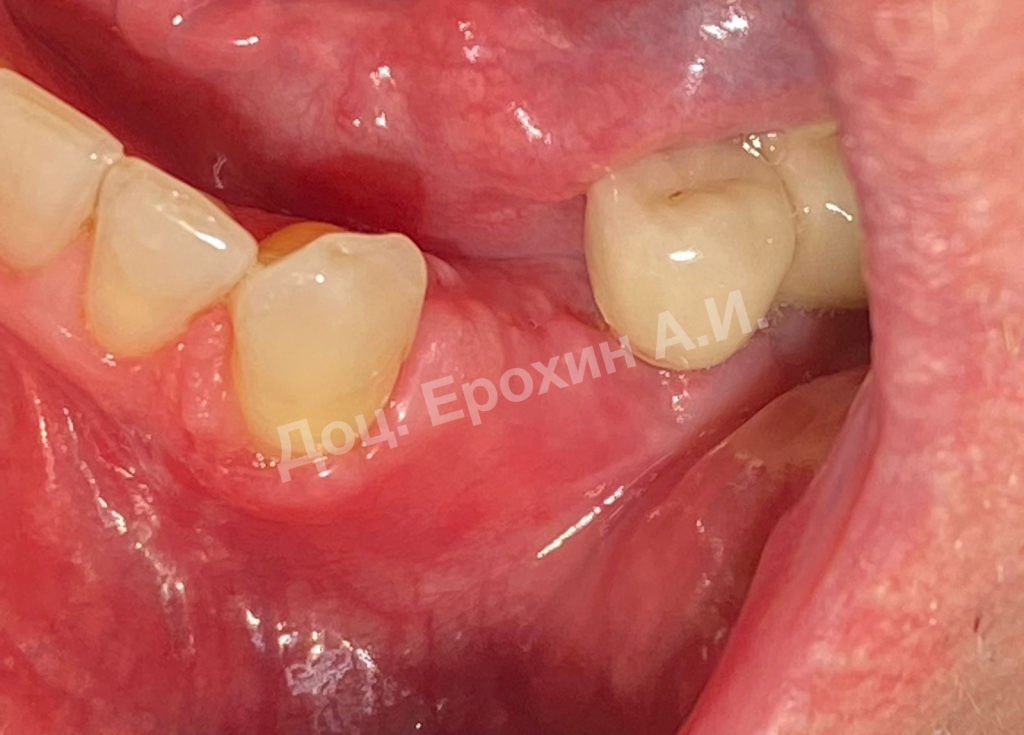

Вертикальные аугментации — самый непредсказуемый тип костной пластики методом НРТ. Мембрана способна коллапсировать, смещая в апикальном направлении костный материал, тем самым полностью нивелирую потраченные усилия.

Тентовые винты имеют широкие шляпки, которые позволяют мембране опираться на них, тем самым препятствуя изменению профиля регенерируемого участка.